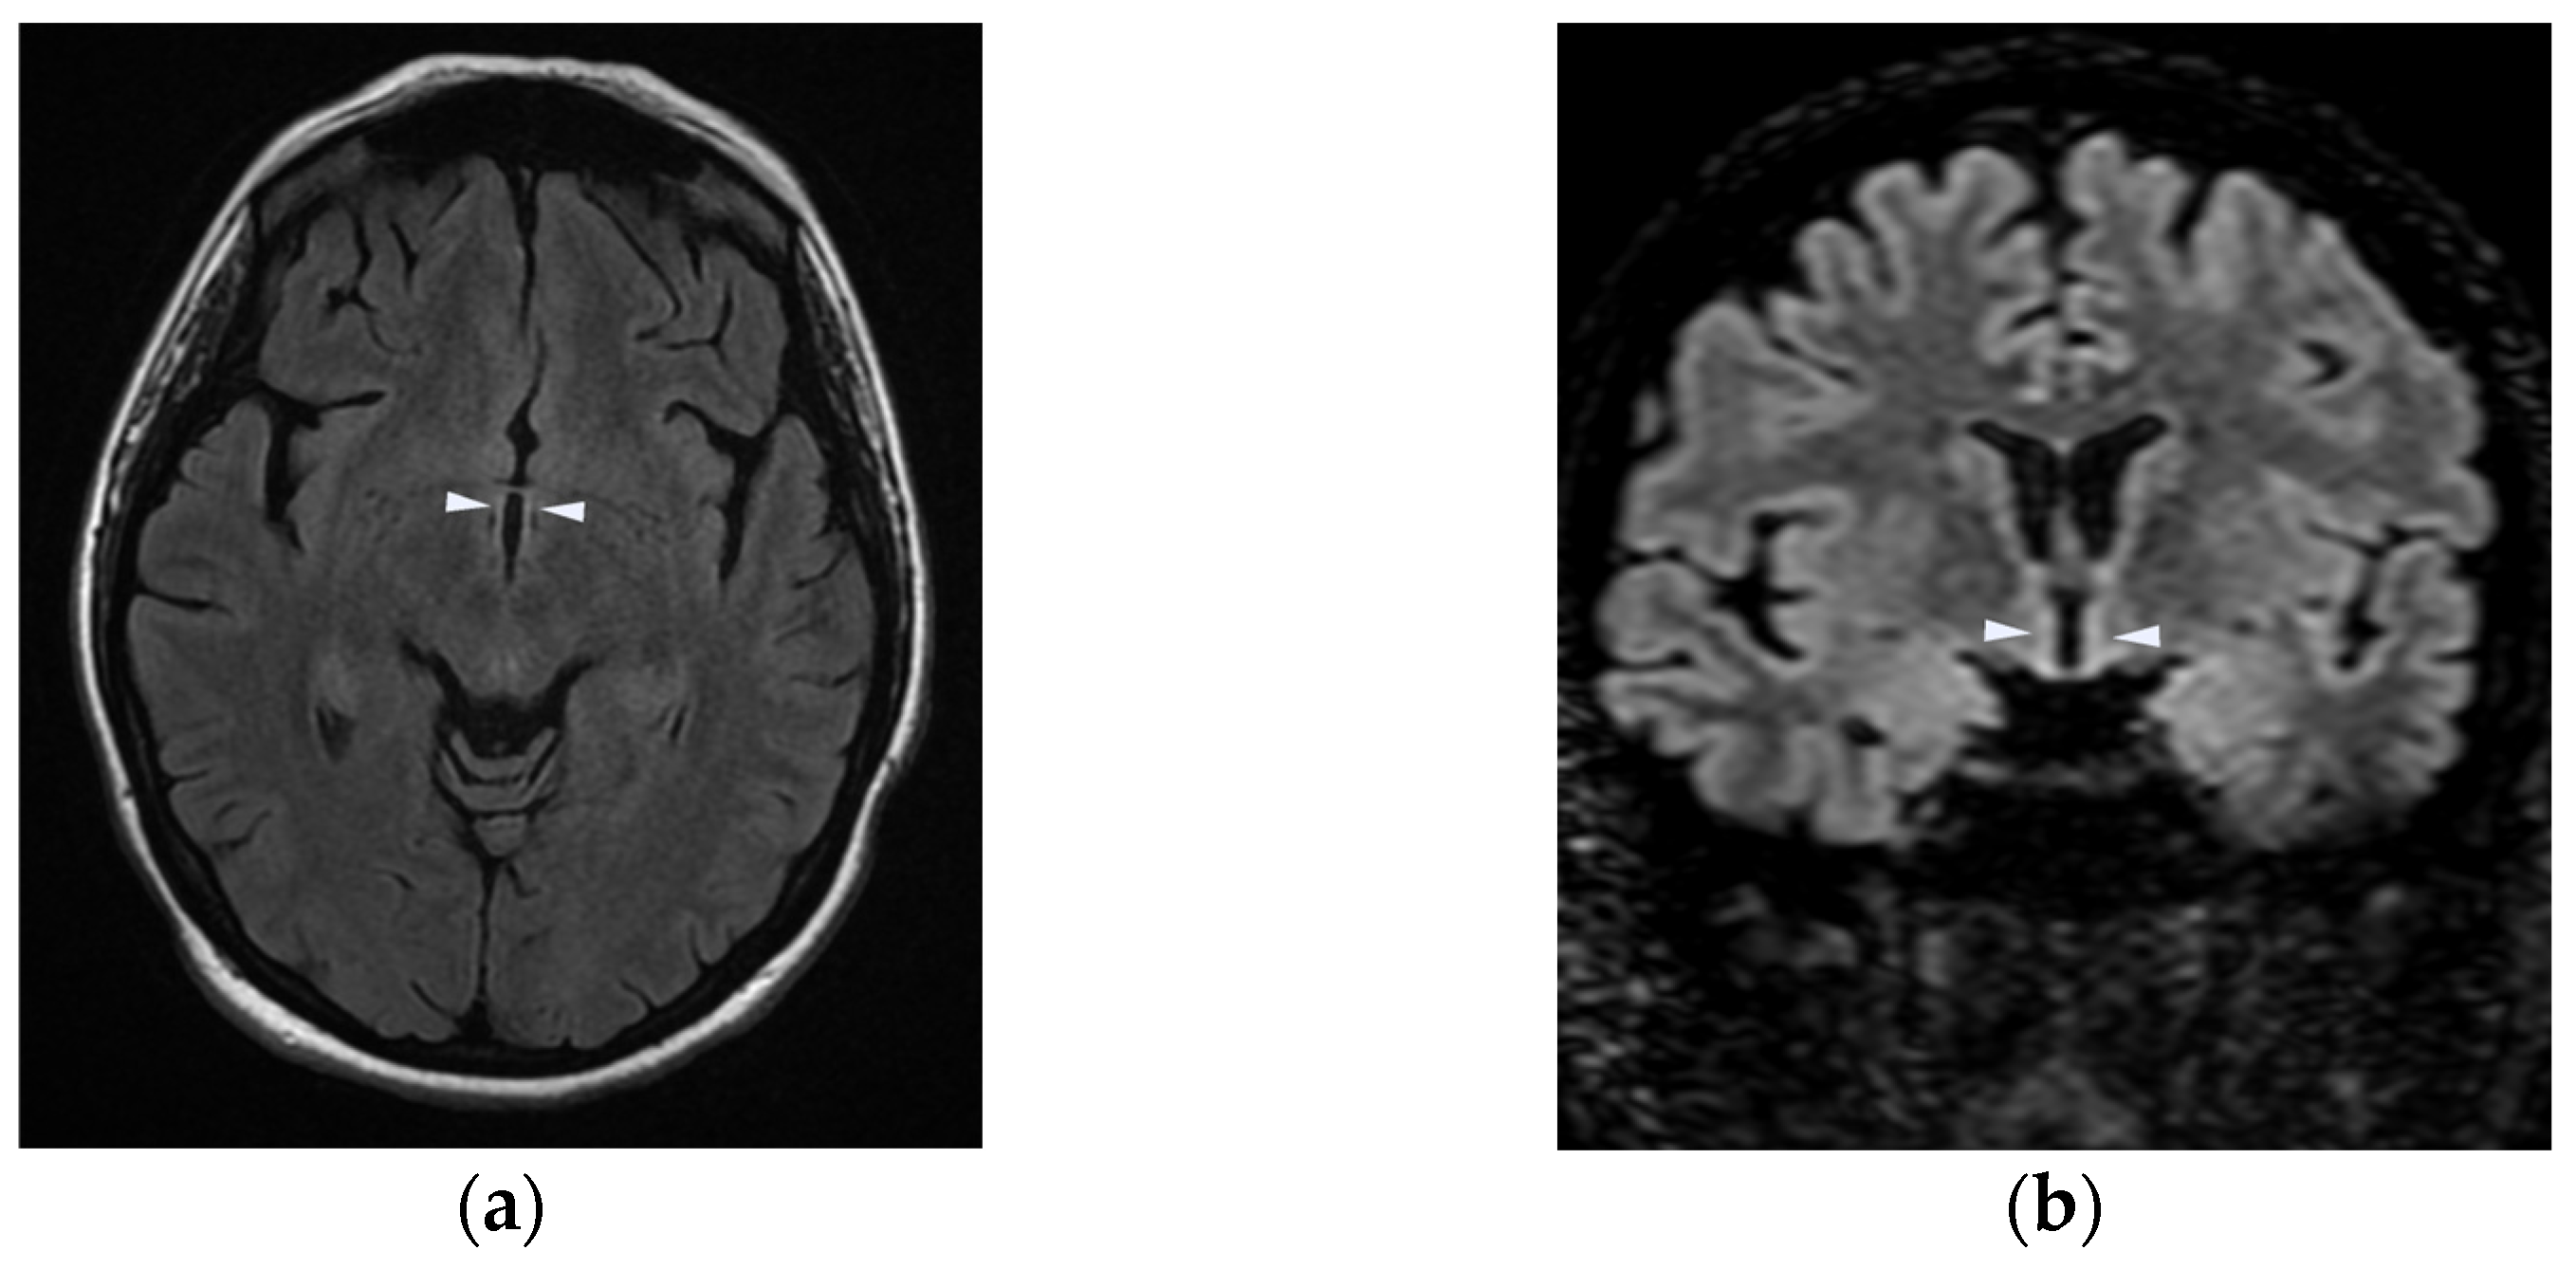

| Brain Imaging | MRI of the brain and spinal cord showed hyperintensity of:

|